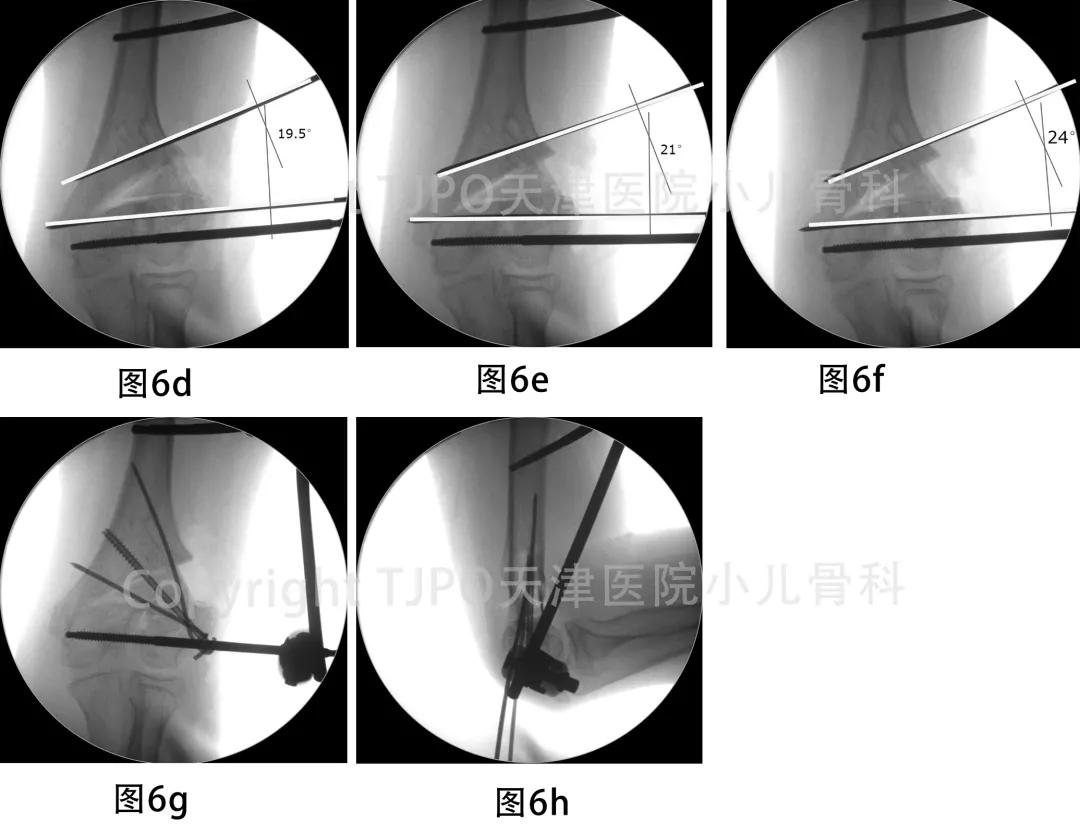

二期手术行内固定取出,肱骨髁上开放截骨矫形。考虑如行闭合楔形截骨可能引起上臂短缩,双侧不对称,故选择行外侧开放楔形截骨,使用外固定支架固定,以更好的实现外侧撑开,加用植骨及克氏针+空心钉固定,以维持矫形端稳定。矫正后术中检查左肘屈伸活动良好(图6)。

图6a-图6c 取出内固定后,在拟截骨远近端各打入一枚定位导针,两导针相互平行,指示截骨撑开角度。分别平行两枚导针钻入两枚外架半钉。近端置钉时注意保护桡神经。在肱骨髁上水平平行于关节面做截骨,尽量保留内侧铰链完整

图6d-图6h 截骨断端撑开,调整矫形角度,位置满意后锁紧外架,补充克氏针+空心钉固定三角骨块及截骨端